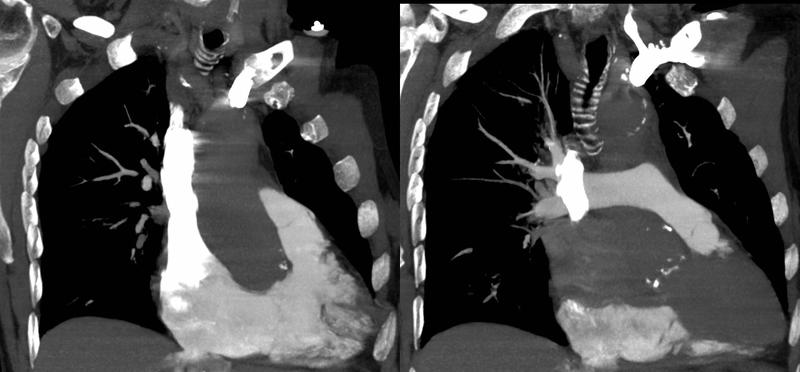

Rt heart